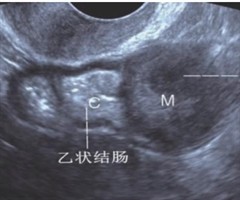

乙状结肠神经鞘瘤超声诊断一例及文献复习

摘要:乙状结肠神经鞘瘤是一种罕见的胃肠道良性肿瘤,术前很难明确诊断。本文报道1例乙状结肠型神经鞘瘤,术前超声检查诊断为间质瘤,术中冰冻切片诊断为梭形细胞肿瘤,最后经免疫组织化学确诊为胃肠道神经鞘瘤。本文总结了肠道间质瘤与神经鞘瘤在超声声像图...